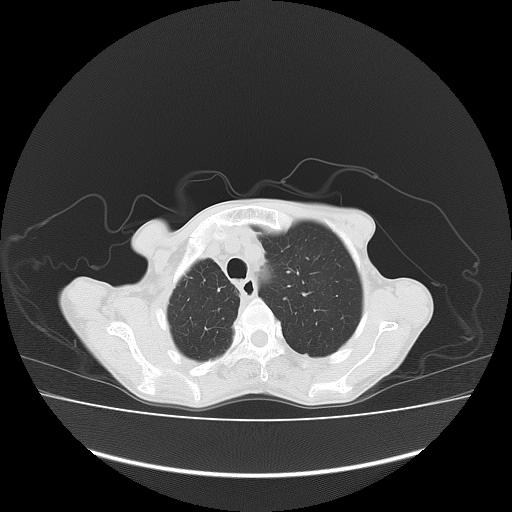

右侧胸膜增厚,局部呈结节状增厚,右侧胸腔少量积液。双肺未见确切肿块影。纵隔未见淋巴结肿大。气管、支气管通畅。考虑右侧胸膜间皮瘤(恶性?)可能性大。不除外癌性胸膜炎。

右侧广泛胸膜增厚,局部呈结节状增厚,右侧胸腔少量积液。双肺未见确切肿块影。纵隔未见淋巴结肿大。气管、支气管通畅。考虑右侧胸膜间皮瘤(恶性?)可能性大。支持!

恶性胸膜间皮瘤伴肺内转移可能性大;或胸膜、肺内均为转移瘤,左肺下叶亦见多发小结节影。